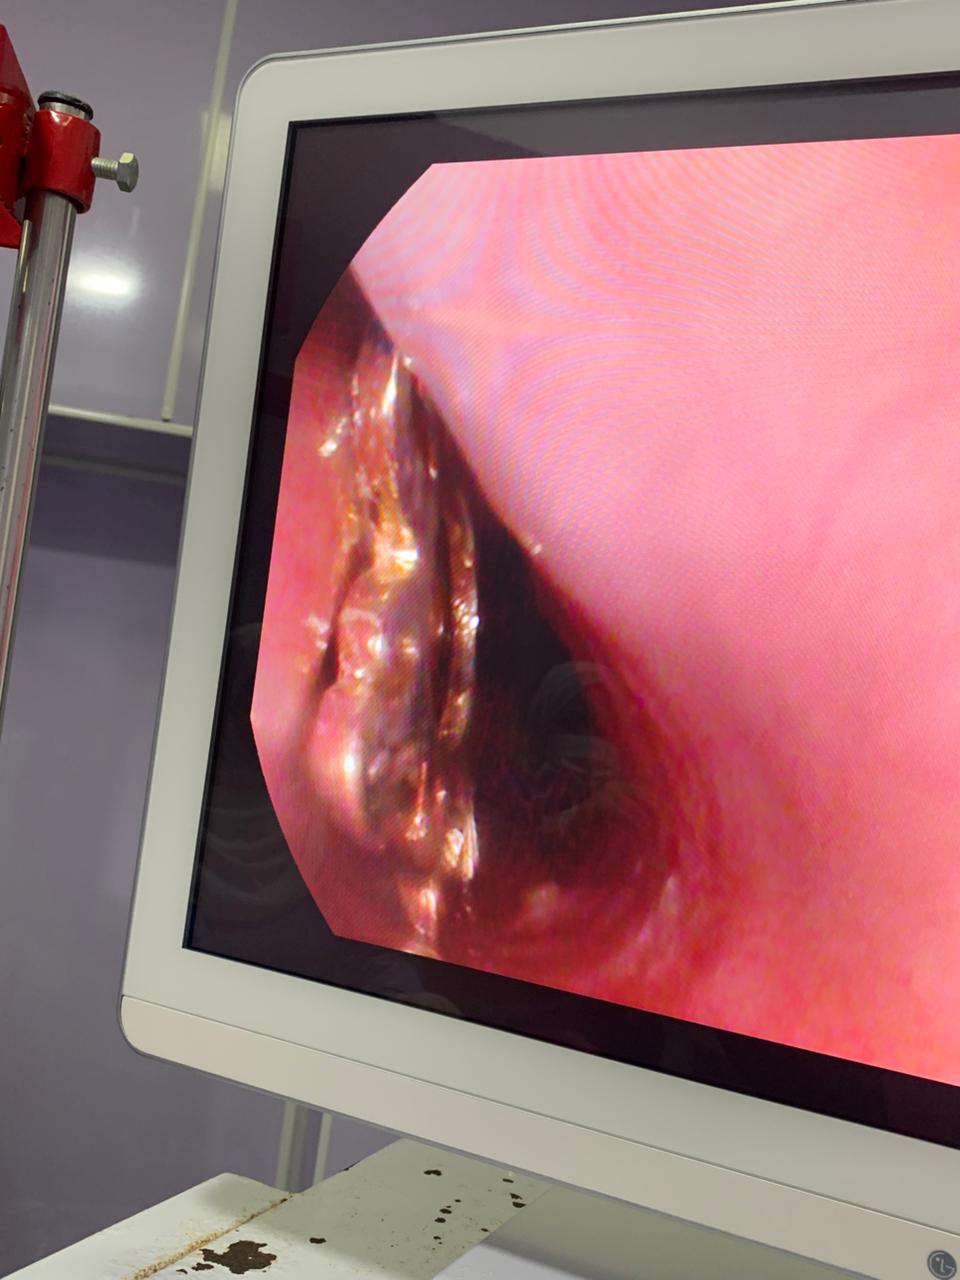

وأوضح الدكتور أحمد البيلي وكيل وزارة الصحة أن قسم المناظير بمستشفى أبو كبير شهد نجاح مميز في إنقاذ الطفلة التي تبلغ من العمر ٥ سنوات، وقامت بابتلاع سلسلة معدنية حادة ومدببة وأطرافها قادرة على إحداث جروح أو ثقوب بالزور أو داخل المعدة، وبعد استقبالها مساء أمس الثلاثاء بمستشفى مشتول السوق المركزي، وتم التنسيق السريع من خلال مركز الخدمات الطارئة ١٣٧ بالمديرية، وتحويل الحالة بسيارة الإسعاف إلى مستشفى أبو كبير في وقت قياسي، وتم التدخل العاجل بالمنظار بعد إجراء كافة الفحوصات الطبية اللازمة لها، واستخراج السلسلة من المعدة دون أي مضاعفات، وسط متابعة وتدخل فوري من الفريق الطبي بقيادة الدكتور محمد عصام خلال الفترة المسائية.

وأضاف وكيل وزارة الصحة بالشرقية بأن الفريق الطبي بقسم مناظير الكبد والجهاز الهضمي بالمستشفى، قام أيضاً بإجراء ٩ مناظير قولونية ومناظير معدة تشخيصية وعلاجية، منهم منظار لمريضة تعاني من قيء دموي حاد نتيجة نزيف من دوالي المعدة وتم حقنها بالمنظار العلاجي، كما تم استئصال زوائد لحمية متعددة بالقولون لمريض آخر يعاني من نزيف شرجي مستمر، هذا بالإضافة إلى إجراء منظار قولوني لطفل يبلغ من العمر ٤ سنوات يعاني من إمساك مزمن ونزيف شرجي، وتم أخذ عينات من قرح وزوائد بالأمعاء الدقيقة لتحليل الأنسجة.